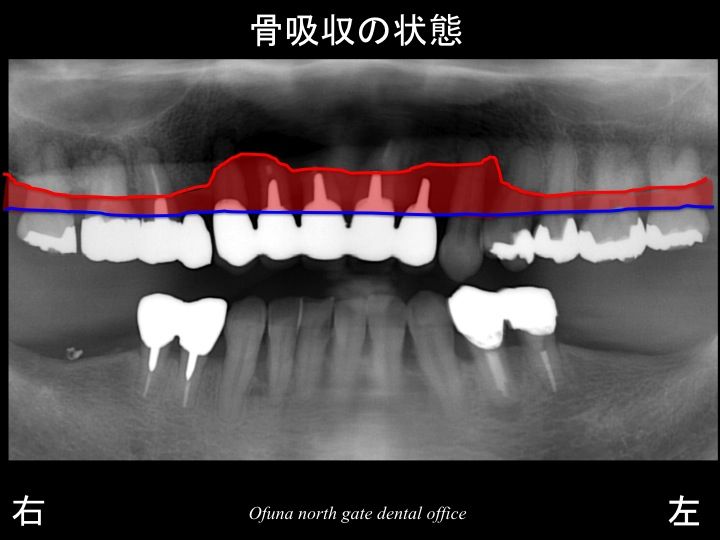

いつものように 骨吸収の状態を分かりやすくするために

骨吸収の状態を線で書いたのが以下のレントゲンになります。

青線が骨吸収を起こす前の骨の位置です。

赤線は、現在の骨の位置です。

かなりの骨吸収が起こっているのが分かるかと思います。

さらに わかりやすくするために、

骨吸収部位を赤色で表示します。

骨吸収が本当にすごいですね。

歯を支えている骨が吸収するため、歯がグラグラするのです。